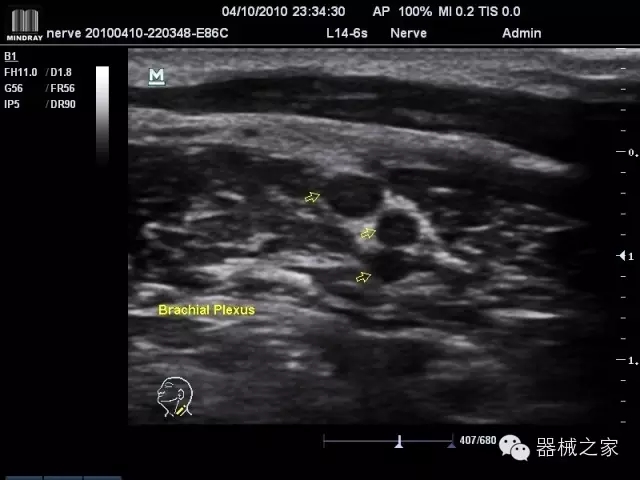

臨床圖片賞析

·優(yōu)秀的圖像效果、強(qiáng)大的功能體驗(yàn)、豐富的探頭選擇、合理的便攜式設(shè)計(jì),全中文顯示及病人管理界面,使得M7在任何場合、任何時(shí)候都能快速響應(yīng)更好的心血管、腹部、婦產(chǎn)、小器官等常規(guī)超聲檢查以及肌骨、神經(jīng)、顱腦、術(shù)中等新興領(lǐng)域的使用需求;